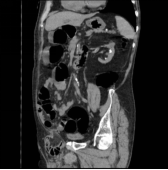

俯卧超薄断层像

MPR图像:多方位观察大肠病变的三维形态及与周围的毗邻关系。

冠状位

矢状位

斜冠状位